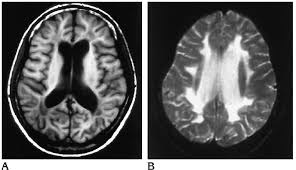

Contributor: Aaron Lessen, MD Educational Pearls: The cause of Alzheimer's disease is multifactorial, but the most widely suspected mechanism is the amyloid cascade hypothesis: Beta-amyloid proteins accumulate in the central nervous system, forming plaques that impair neuronal function. In recent years, advances have led to the development of targeted therapies with monoclonal antibodies. These drugs: Work by degrading amyloid plaques Slow the rate of cognitive decline and disease progression Have major side effects, most notably the development of amyloid-related imaging abnormalities (ARIA) ARIA may present as edema, effusion, or microhemorrhages, which are only detectable on MRI Symptoms can include headache, vertigo, or focal neurologic deficits that mimic stroke For patients presenting to the emergency department with stroke-like symptoms, it is important to consider whether they have a history of Alzheimer's disease and whether they are taking these medications. This guides decisions about imaging and treatment: The work-up may require MRI, which can delay thrombolytic or endovascular therapy in patients with true strokeConversely, treating a patient with ARIA using thrombolytics increases the risk of bleeding and other complications References Ebell MH, Barry HC, Baduni K, Grasso G. Clinically Important Benefits and Harms of Monoclonal Antibodies Targeting Amyloid for the Treatment of Alzheimer Disease: A Systematic Review and Meta-Analysis. Ann Fam Med. 2024 Jan-Feb;22(1):50-62. doi: 10.1370/afm.3050. PMID: 38253509; PMCID: PMC11233076. Ma C, Hong F, Yang S. Amyloidosis in Alzheimer's Disease: Pathogeny, Etiology, and Related Therapeutic Directions. Molecules. 2022 Feb 11;27(4):1210. doi: 10.3390/molecules27041210. PMID: 35209007; PMCID: PMC8876037. Perneczky R, Dom G, Chan A, Falkai P, Bassetti C. Anti-amyloid antibody treatments for Alzheimer's disease. Eur J Neurol. 2024 Feb;31(2):e16049. doi: 10.1111/ene.16049. Epub 2023 Sep 11. PMID: 37697714; PMCID: PMC11235913. Summarized by Ashley Lyons, OMS3 | Edited by Ashley Lyons and Jorge Chalit, OMS4 Donate: https://emergencymedicalminute.org/donate/